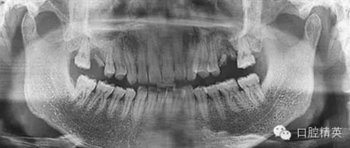

3個(gè)月后來進(jìn)行種植手術(shù),頜骨曲面斷層片

檢查口腔種植區(qū)骨和粘膜厚度為7.5MM。齦顏色正常,無瘺道。種植區(qū)牙槽骨密度接近正常,竇嵴距10MM,左上頜竇無明顯炎癥影像。排除曲斷這個(gè)位置的20%放大率,擬做上頜竇內(nèi)提升后種植ITI的10MM的種植體。